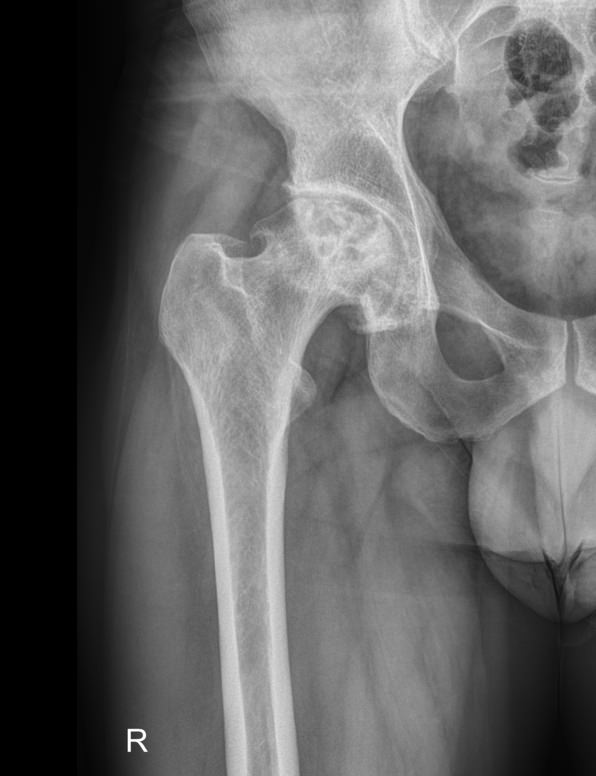

Рентгенография ― один из классических видов диагностики костей и суставов. Костная ткань, как наиболее плотная в организме, поглощает больше всего излучения и на стандартном негативном снимке выглядит самой светлой. При этом ясно видны все патологические изменения: разрежение и новообразования костей, утолщение или расслоение надкостницы, вывихи и переломы.

На рентгене можно обнаружить такие элементы тазобедренного сустава:

• Вертлужная впадина, сформированная из подвздошной, седалищной и лонной костей;

• Головка, шейка и другие образования бедренной кости;

• Суставная щель.

Их изменения говорят об острой или хронической патологии данной области.

В протоколе подробно описывают:

• Состояние мягких тканей ― в норме или есть признаки изменений;

• Суставную щель ― ширина нормальная или измененная, равномерно или нет, затенена или обычая, есть ли краевые костные разрастания или обломки кости;

• Конгруэнтность/соответствие головки и впадины ― норма, вывих, подвывих;

• Структуру кости, надкостницы ― обычные или патологические;

• Новообразования, если есть ― их размеры и локализацию.